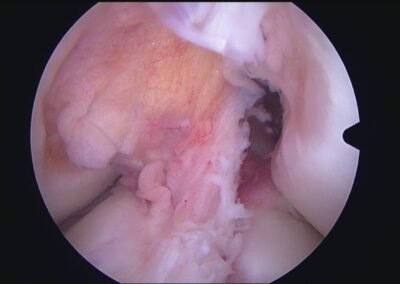

GalleryShoulder rotator cuff repair Meniscus root repair Meniscus repair Bankart repair for recurrent shoulder dislocation ACL reconstruction Machines Instruments